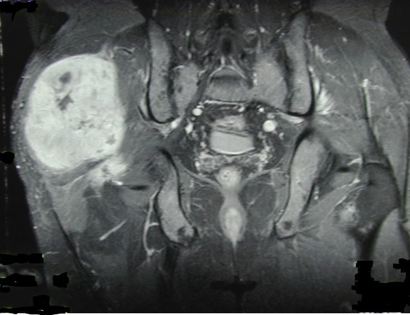

On this MRI, the tumor can be identified as the brightened portion on the left hand side of the image. Although it is the left side of the image, it is actually on the right side of the human.